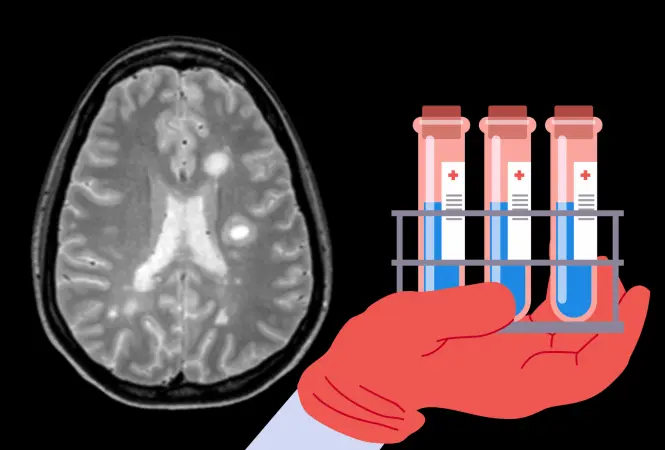

Wie können Roboter und Menschen in Zukunft bestmöglich im OP zusammenarbeiten? Das haben Forschende der Technischen Universität München (TUM) und des TUM Klinikums im Forschungsprojekt ForNeRo untersucht.